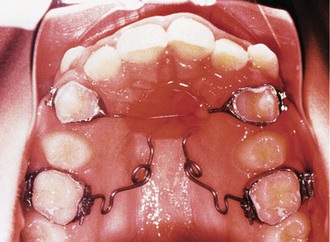

Figure 12-4 Class II, Division 1 malocclusion treated with a vertical holding appliance (VHA). A–E, Pre-treatment intraoral photographs of a Class II, Division 1 subdivision left malocclusion. F–J, Progress photographs showing a VHA cemented to the maxillary first molars and a fixed lingual arch (FLA) cemented to the mandibular first molars. These photographs were taken 6 months after delivery of the VHA and FLA. K–O, Final records at completion of treatment.